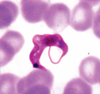

What findings on blood smear confirm a diagnosis of malaria?

Trophozoite ring forms within red blood cells and schizonts containing merozoites